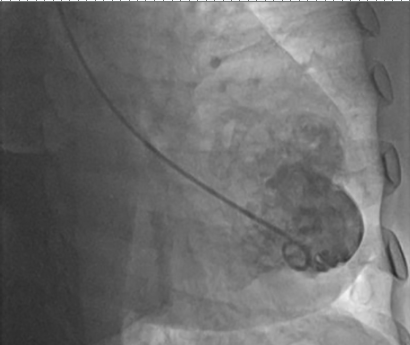

Ventriculografia: ao injetar contraste há a presença de extravasamento de contraste (seta branca):